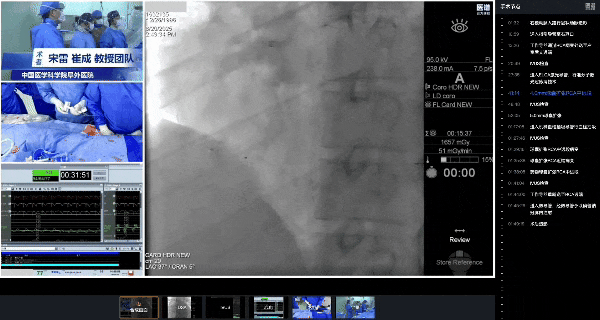

手术复盘过程

过导丝

术中经右桡动脉入路完成造影后,顺利将指引导管送至右冠口。在尝试通过导丝时,由于右冠近段血管粗大且分支较多,导丝多次进入分支血管,通过困难。随后调整为分步推进策略:先将一根导丝选择性送入分支,以调整导管方向并增强支撑,再沿该导丝顺利将第二根工作导丝送入目标主支远段,之后撤出分支内的首根导丝。工作导丝在通过第二转折处时,经反复调整与耐心操作,成功跨越RCA病变部位,抵达左室后支远段。

过导丝并评估血管内部情况

血栓消蚀和球囊扩张

随后,IVUS评估显示,右冠脉管径过大,且机化血栓负荷重,如直接植入支架/放置药球可能导致支架贴壁不良/药球膨胀不全及血流恢复不佳等,决定在支架植入/药球放置前先行血栓消蚀。

消蚀过程中,首先使用1.7mm ELCA激光导管,在第二转折处及其邻近区域实施准分子激光冠状动脉消蚀术,并配合持续生理盐水灌注,采用反复、缓慢的消蚀策略,逐步扩大真腔。随后,换用4.0 mm球囊对右冠中远段进行充分扩张后,IVUS提示管腔已趋于融合,但仍见低密度贴壁血栓及明显的腔内分隔。鉴于血管直径超过6 mm,升级为5.0 mm球囊,在第二转折处狭窄部位及右冠中段进行反复扩张,以进一步建立较大、形态完整的管腔通道。

4.0mm球囊扩张